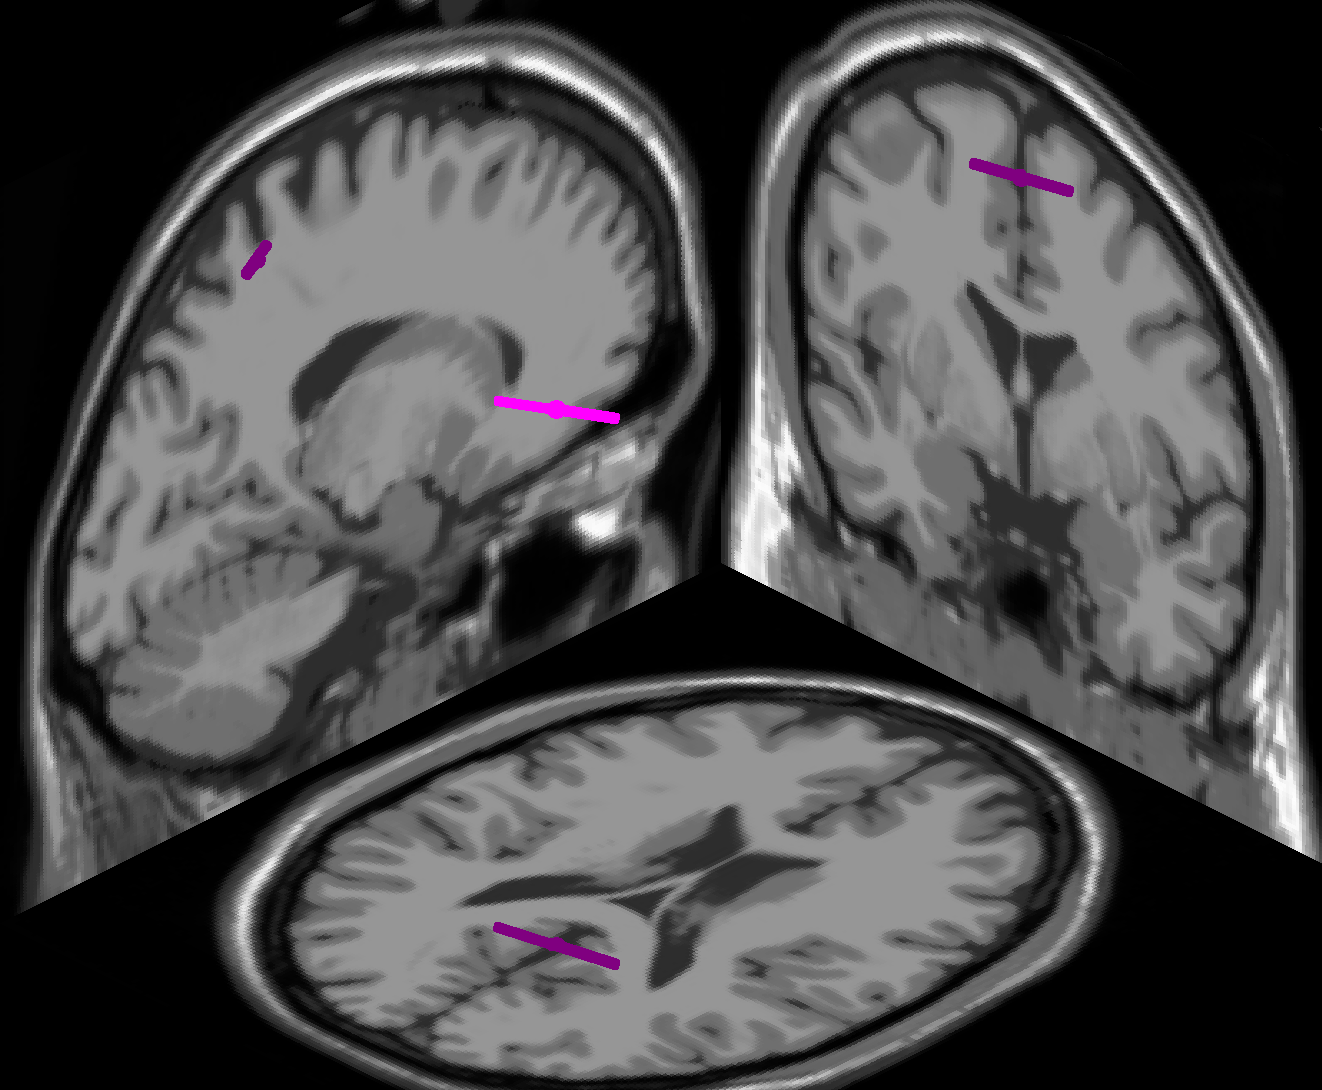

We first high-pass filtered the resting-state data of each subject at a cut-off frequency of 3 Hz, and then performed a group-wise ICA on the combined resting-state data of all subjects. We chose the SOBI algorithm [2] for this purpose, as ICA algorithms based on second-order statistics have been shown to outperform methods based on higher moments in group-wise analyses [21]. We manually inspected the topography and spectrum of every resulting independent component (IC) and rejected all ICs as non-cortical that did not exhibit a clear dipolar topography [9]. The topographies and equivalent dipoles of the six cortical ICs that we retained for further analyses are shown in figure 3. Equivalent dipole locations were derived with a three-shell spherical head model with standardized electrode locations, using the EEGLAB toolbox [8]. We note that ICs 1 and 2, located in sensorimotor and occipital cortex, represent sensorimotor and low-level visual processes, respectively. In contrast, ICs 3, 4 and 5, located in precuneus, in the anterior cingulate, and at the intersection of cuneus and precuneus, respectively, are generated in cortical areas linked to fronto-parietal attention networks [5]. IC 6 appears to represent a sub-cortical source.

Refer to caption

(a) IC 1, RV 5.88%

(b) IC 2, RV 3.28%

(c) IC 3, RV 4.39%

(d) IC 4, RV 3.25%

(e) IC 5, RV 3.07%

(f) IC 6, RV 1.88%

Figure 3: Topographies and equivalent dipole locations of the six cortical ICs from the group-wise ICA. The residual variances of the equivalent dipole fits are denoted by RV.